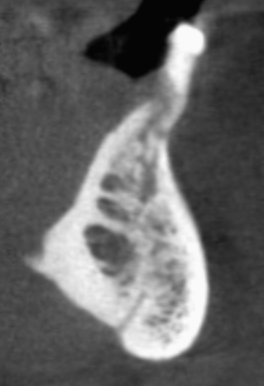

cone beam CT

The patient is seated in the chair. The machine rotates around the head & emits a collimated cone-shaped x-ray beam. The scan takes 9.6 seconds. 512 computer files are generated. With special software, it is possible to create any number of views from any angle in both 2D and 3D. The examples below show some of the possibilities of this technology.

implants